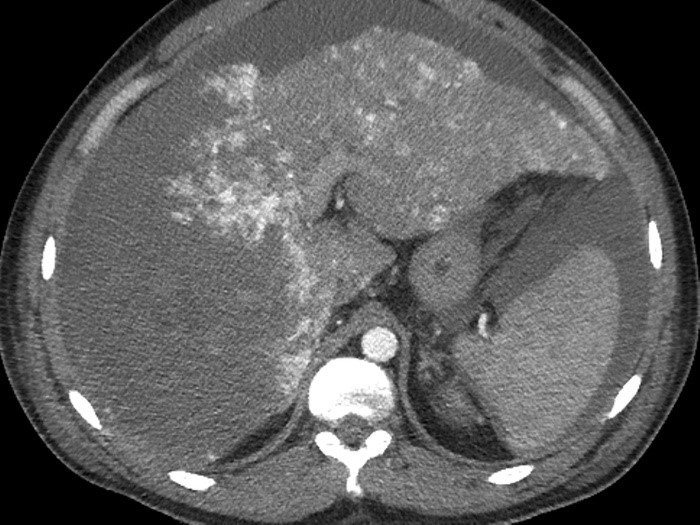

• NET-in qaraciyər metastazlarının xarakterik xüsusiyyəti hipervaskulyar olmasıdır ki, bu da Doppler müayinəsində intensiv axın şəklində, kontrastlı müayinələrdə isə arterial fazada kontrastlaşma və venoz fazada yuyulma əlaməti ilə təyin edilir.

• Hormonal aktiv şişlərdə endokrin əlamətlərlə yanaşı qanda hormonların səviyyəsi artır.

• Funksional karsinoidlərdə sidikdə 5-hidroxiindol turşusunun təyini, adacıq şişlərində isə hormonların təyini diaqnozda faydalıdır.

• Adacıq şişlərinin yayılmasını və diaqnozunu dəqiqləşdirmək üçün PET-KT və somatostatins sintoqrafiyası faydalıdır.

• Histokimyəvi müayinədə xromoqrafin A və neyron – spesifik enolazanın tapılması diaqnozu dəqiqləşdirir.

Diaqnostik əlamətləri:

• Kütlə effekti və ya endokrin əlamətlər

• 5-hidroksiindol turşusu və ya hormonların artması

• Hipervaskulyar törəmələr

• PET-KT və ya somatostatin ssintoqrafiyası müsbət

• Biopsiyada xromoqrafin A, neyronal enolaza enzimi müsbət